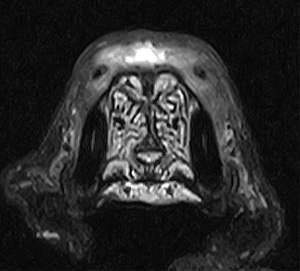

5~6歳以上の去勢手術をしていないオス犬に多い病気ですが、メス犬や去勢した犬に起こることもあります。お尻の筋肉が萎縮した結果、筋肉の隙間から直腸や膀胱が皮膚の下にとびでてしまいます。これにより便が出にくくなったり膀胱炎になったりします。手術をすることで機能回復および今後の致死的な状況を回避することができます。当院では去勢手術→結腸固定→前立腺固定→骨盤隔膜構成筋の縫縮→内閉鎖筋フラップ→浅臀筋フラップの順で通常腹側・臀部左右両側同時に行います。また老化以外に、筋肉が萎縮する原因があったり、腹圧がかかる原因があったりする場合も多いので、再発防止のためそれらの診断・治療も重要です。今回のワンちゃんも無事手術も終わり元気に退院しました。よかったね。